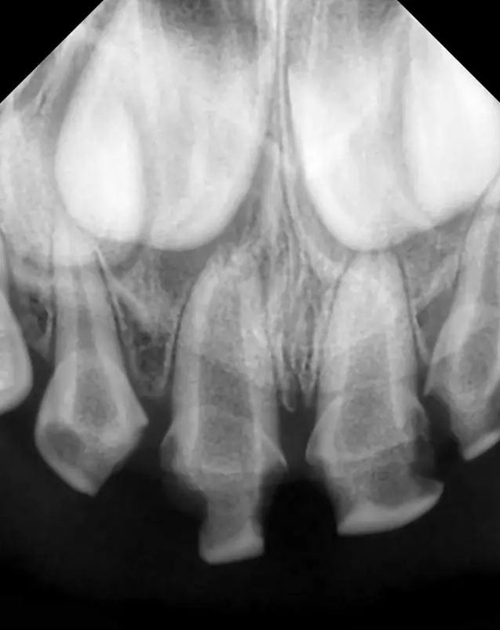

檢查:51,殘冠,牙合面齲壞達(dá)牙本質(zhì)深層,冷熱診無(wú)反應(yīng),探診(-),叩痛(+),唇側(cè)牙齦見瘺管,X線示根尖部見大面積低密度陰影;52,61,62頸部環(huán)狀齲壞達(dá)牙本質(zhì)深層,冷熱診敏感,探診(+),叩痛(-),X線示齲壞低密度陰影與髓腔連通。

診斷:51 根尖周炎

52,61,62  牙髓炎